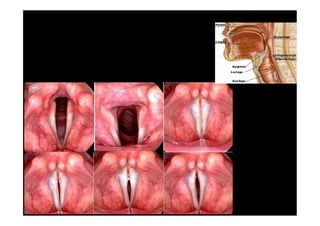

LARINGE – PREGAS VOCAIS

LARINGE: tubo muscular que permite a

passagem do ar para a traquéia.

LARINGE – EPIGLOTE: lâmina(válvula) que

impede a comunicação da laringe com a glote,

impedindo a entrada dos alimentos.